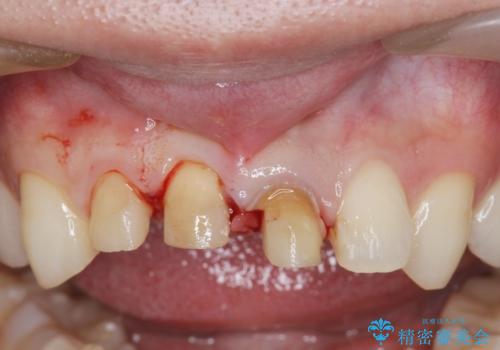

・歯肉縁下カリエス →部分矯正による歯の挺出・歯周外科

歯の挺出を行ったことで歯ぐきの腫れも改善され、安定した歯周環境下でのセラミッククラウン治療を行うことができました。